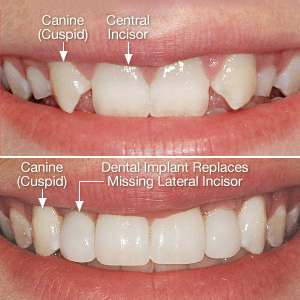

Diş hekimi hilal yıldız yüksel implant eksik estetik diş diş beyazlatma ve diş eti tedavi için şişli diş hekimi tel 0544 3470347.